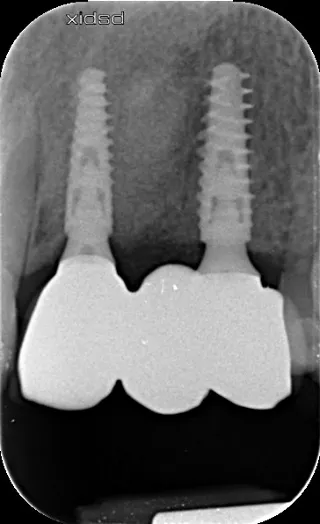

17a-b-c-d. Retro-alveolar X-rays at the end of treatment. Note bone behavior around the 4 implant collars. Soft tissue height above each collar was 3 to 4 mm.